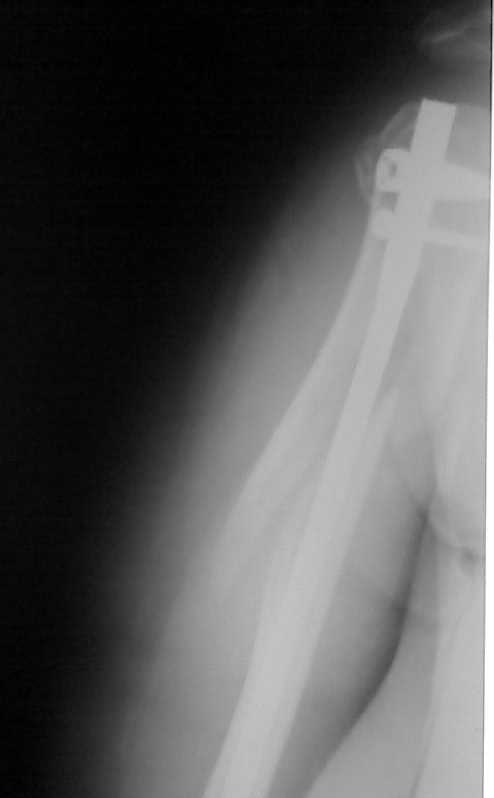

На прошлой неделе прооперировали пожилую женщину с сопутствующим

сахарным диабетом по поводу оскольчатого перелома в/3 плечевой кости

штифтом PHN фирмы "Mathys". Имеется вот такое стояние костных отломков

(см. рентгенограммы).

Мнения коллег в отделении разделились: одни считают, что стояние

отломков крайне неудовлетворительное и сращение кости при таком

стоянии вряд ли возможно, другие считают, что при закрытом методе

остеосинтеза и стабильной фиксации отломков результат будет

благоприятный и сращение кости, даже при таком стоянии костных

отломков, будет обязательно. Я придерживаюсь последнего мнения.